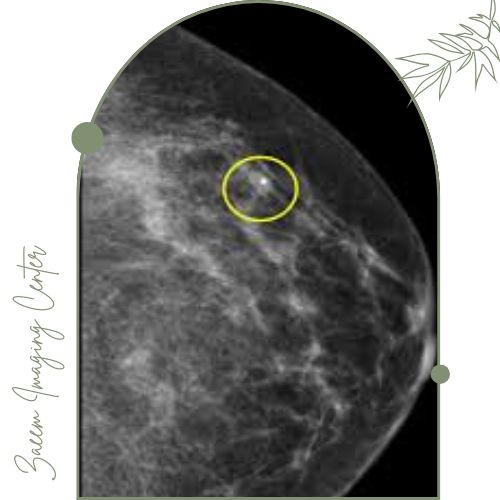

مارکر گذاری پستان یکی از روش‌های تصویربرداری و مداخله‌ای تخصصی در رادیولوژی است که با هدف محل‌یابی دقیق ضایعه یا توده‌های مشکوک قبل از جراحی یا نمونه‌برداری انجام می‌شود. در این تکنیک یک مارکر کوچک (معمولاً از جنس فلز یا ترکیبات سازگار با بدن) تحت هدایت سونوگرافی یا ماموگرافی دقیقاً در بافت پستان و کنار یا داخل ضایعه قرار داده می‌شود.

قرار دادن مارکر: بر اساس تصویر لحظه‌ای توسط سونوگرافی یا ماموگرافی مارکر در محل ضایعه یا کنار آن قرار داده می‌شود.

تأیید محل: تصویربرداری مجدد برای اطمینان از جای صحیح مارکر.